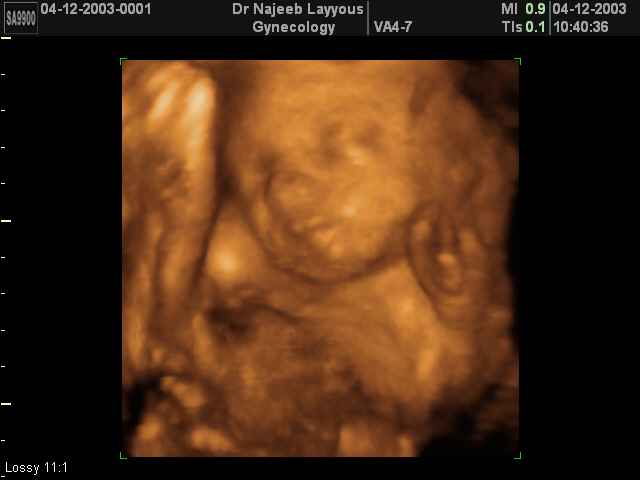

صور لوجه الجنين بجهاز الالتراساوند ثلاثي الأبعاد | الدكتور نجيب ليوس

صور لوجه الجنين بجهاز الموجات فوق صوتية ثلاثي الأبعاد